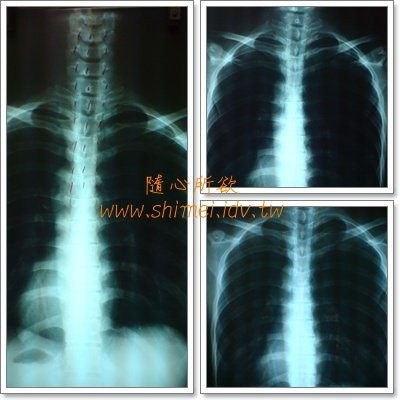

這是這幾年拍的X光片-胸椎

它的發展史:由左而右,由上而下

左邊第一張,是九十五年拍的

當時X光片洗出來時,阿軒都以為,對方拿錯了

沒想到,阿軒真的是有點歪啊!

隔年九十六年五月拍了右上角那張

看起來,比左邊第一張好多了

至於,為何又拍了第三張,也就是今天,九十七年六月拍的

是因為在療程中,壓到胸椎某一點時,會很痛不舒服

所以,才拍這張,想確認看看

不過,看起來,好像,還OK耶!

那就不懂,為何那點....會痛了!=_=